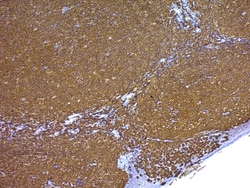

Pre-process tissue treatment reagents designed to improve and expedite subsequent processes; used to increase immunoreactivity and automate processes; for heat-induced epitrope retrieval, antigen retrieval, and more.

10X Tris-EDTA Buffer For Heat Induced Epitope Recovery, pH 9.0 is designed for use during the heat induced epitope retrieval (HIER) step prior to immunohistochemistry on formalin-fixed paraffin embedded tissue sections. The use of this buffer in combination with heat (often by microwave, water bath, or pressure cooker) has been shown to restore the antigenicity of proteins modified during the formalin fixation of tissue. This buffer is supplied as a 10X stock solution.

Antigen Retrieval Reagent, pH 9 (10X) is used to recover antigens masked by fixation in cross linking fixatives such as formalin. Formulation: Liquid. In Tris-EDTA buffer. Long Term Storage: +4°C. Applications: IHC .

Antigen Retrieval Reagent, pH 6 (10X) is used to recover antigens masked by fixation in cross linking fixatives such as formalin. Formulation: Liquid. In citrate buffer. Long Term Storage: +4°C. Applications: IHC .